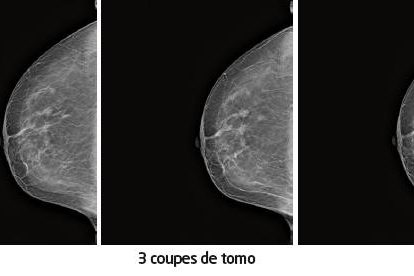

QUIZZ IMAGE 184

Proposé par le Dr Joël CRÉQUAT – Échographiste, Centre Péreire, Paris Contexte clinique Il s’agit de l’échographie d’un utérus en coupe sagittale.Le myomètre est homogène.L’endomètre est visible.On y observe 3 images rondes hyperéchogènes de quelques millimètres de diamètre.Qu’en pensez-vous ? Quelles hypothèses évoquez-vous ? Réponse : Il s’agit d’un DIU chinois, inconnu en…